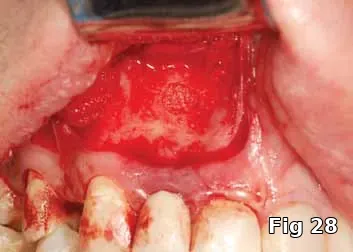

Here is a 24-year-old male with an ASA1 medical status who presented for the treatment of an apical lesion prior to prosthetic replacement of the failing existing restoration secondary to recurrent decay. Treatment plan to perform an apicoectomy and retrofill with MTA with Beta phase Tri Calcium Phosphate (B-TCP) bone graft saturated with PRP for GBR (Fig. 28).

PGRF fibrin membrane was developed and secured into place by resorbable sutures (Fig. 29).